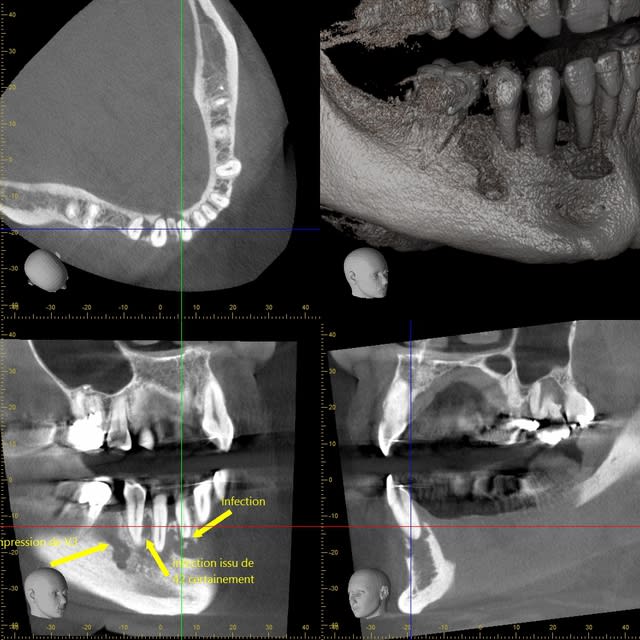

je viens de tomber sur une clé usb avec quelques images...